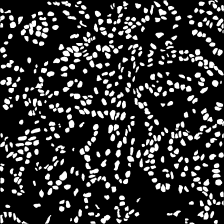

Microscopic image segmentation is a challenging task, wherein the objective is to assign semantic labels to each pixel in a given microscopic image. While convolutional neural networks (CNNs) form the foundation of many existing frameworks, they often struggle to explicitly capture long-range dependencies. Although transformers were initially devised to address this issue using self-attention, it has been proven that both local and global features are crucial for addressing diverse challenges in microscopic images, including variations in shape, size, appearance, and target region density. In this paper, we introduce SA2-Net, an attention-guided method that leverages multi-scale feature learning to effectively handle diverse structures within microscopic images. Specifically, we propose scale-aware attention (SA2) module designed to capture inherent variations in scales and shapes of microscopic regions, such as cells, for accurate segmentation. This module incorporates local attention at each level of multi-stage features, as well as global attention across multiple resolutions. Furthermore, we address the issue of blurred region boundaries (e.g., cell boundaries) by introducing a novel upsampling strategy called the Adaptive Up-Attention (AuA) module. This module enhances the discriminative ability for improved localization of microscopic regions using an explicit attention mechanism. Extensive experiments on five challenging datasets demonstrate the benefits of our SA2-Net model. Our source code is publicly available at \url{https://github.com/mustansarfiaz/SA2-Net}.